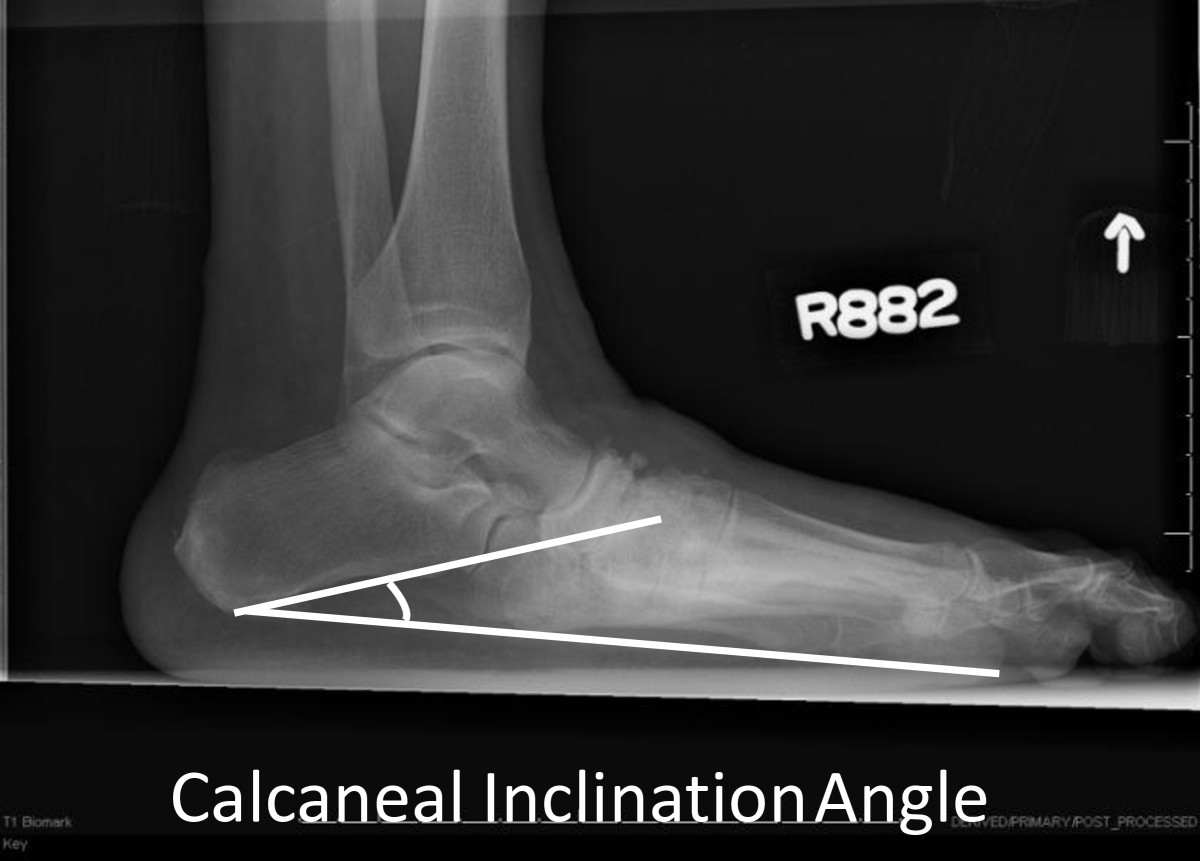

All participants had standardized weight-bearing radiographs of both feet (antero-posterior, lateral and oblique views). A research assistant monitored and standardized each foot position for image consistency and to minimize out-of-plane rotations [3]. A calibration ruler was included in each radiograph to calibrate each image and reduce geometric magnification errors. Radiographs were de-identified of all personal information then uploaded and imported into ISite PACS (Picture Archiving and Communication Systems) workstation software program for measurement (Philips Healthcare Informatics, Foster City, CA). The ISite PACS software measures angles to the nearest 1-degree increment. Talar declination and calcaneal inclination angles were assessed on the lateral view using the angle measurement function in the ISite PACS software. Standard view foot radiographs demonstrate single plane foot deformities. Talar declination and calcaneal inclination angles were selected to represent hind foot alignment changes in the sagittal plane that are best represented by the lateral view foot radiograph. The talar declination angle was measured as the angle formed between the collum tali axis, a line originating from the center of the body of the talus extended through the bisection of the talar neck and head with a horizontal line extending from the plantar surface of the calcaneus to the plantar surface of the 5th metatarsal head [21] (Figure 1). Talar declination angle was measured since it reflects the orientation of the distal head and neck of talus in the sagittal plane and is impaired in flat feet deformities [5]. Calcaneal inclination (pitch) angle was measured as the angle formed between lines extending from inferior portion of the calcaneocuboid joint to the same horizontal line along the plantar aspect of the calcaneus to the plantar surface of the 5th metatarsal head (Figure 2). Calcaneal inclination angle was measured since it reflects the orientation of the anterior calcaneus in the sagittal plane and is impaired in flat feet. The same rater performed radiographic measurements. As reported previously, measurement error as the standard deviation between repeat measurements is 2 degrees for both talar declination angle and calcaneal inclination angles in women 40 to 60 years of age [22]. Hastings et al. recently reported the intra-rater measurement precision of radiographic measures expressed as the root mean square standard deviation (RMS-SD) in participants with DM and PN and foot deformity is 2 to 3 degrees [23]. Both angle measures have been used to describe the alignment of the hind foot bones in the sagittal plane and reflect mid tarsal joint (talonavicular and calcaneocuboid) alignment in acquired neuropathic midfoot deformities [3, 5].

Figure 2

Calcaneal inclination angle formed by the line representing the calcaneal inclination axis drawn from the anterior, inferior calcaneal border of the calcaneocuboid articulation and a line representing the weight bearing plantar surface from the calcaneus to the 5th metatarsal.